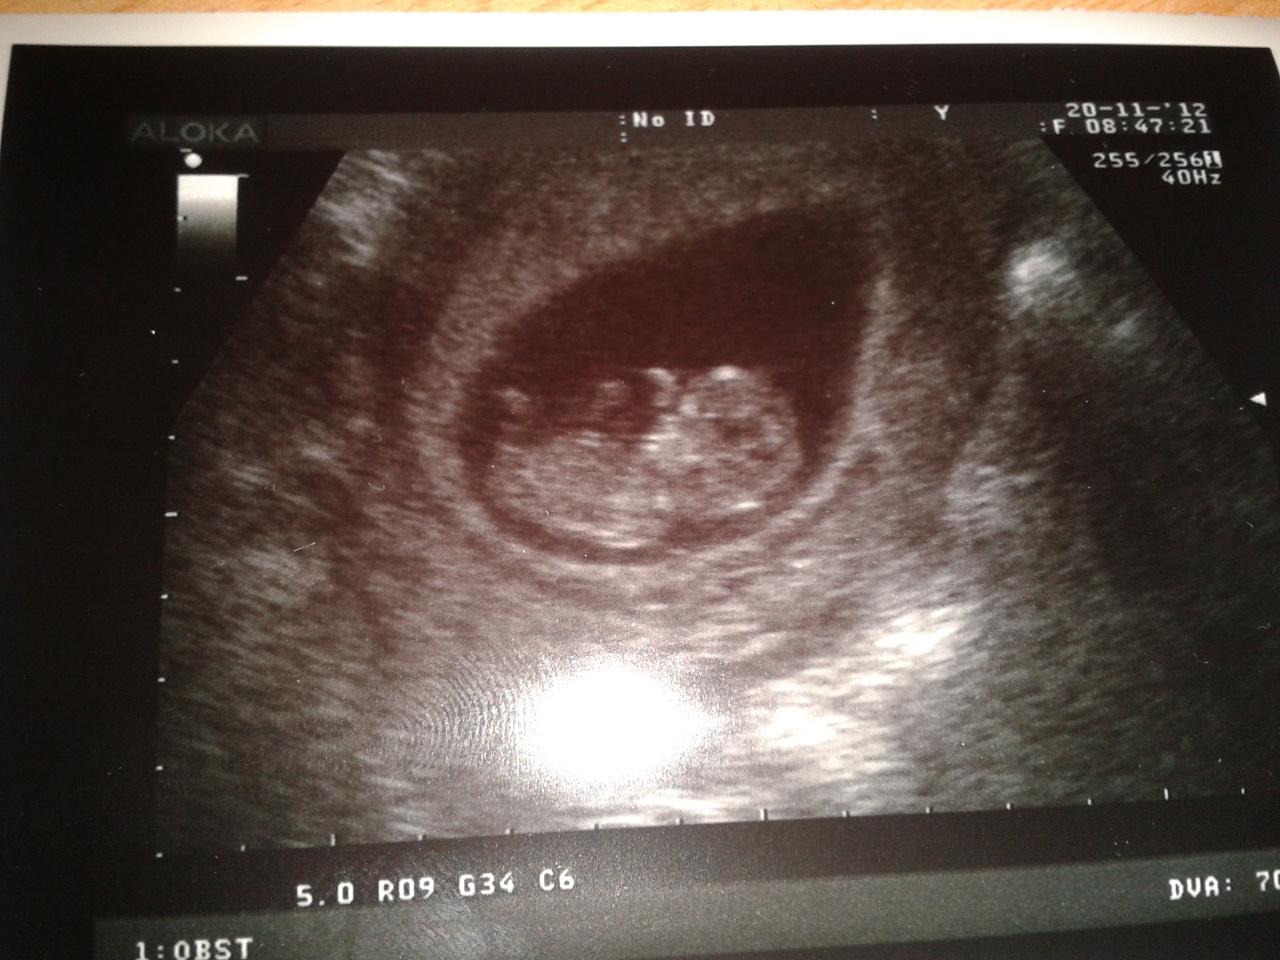

Zdravíme holky 🙂 tak jsem misto čtvrtka jeli do poradny dneska 🙂 protože auto jde do servisu a neměla bych se jak dostat. Miminko je vpořádku, roste jak z vody dnes jsme 10+6tt byli jsme na krev na screening a 5.12.jdeme na genetický ultrazvuk pujde poprvé i tatka tak se moc těší 😉 😉 pohladte bříška

přidávám prcoška 🙂